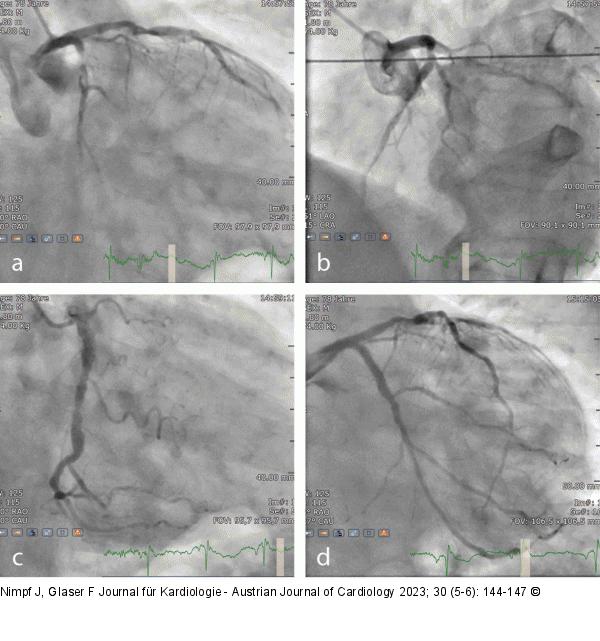

Abbildung 4a-d: Angiographie (a-c) Diagnostische Angiographie; (d): nach CX-Intervention |

Abbildung 4a-d: Angiographie

(a-c) Diagnostische Angiographie; (d): nach CX-Intervention |